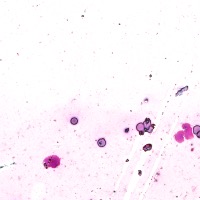

Medical Diagnosis: The "4class" model can be employed by pathologists to accurately identify and quantify the different cell types in blood and tissue samples, assisting in the diagnosis of various blood disorders and diseases, including anemia, leukemia, and infections.

Research and Drug Development: Researchers can use the "4class" model to analyze cellular response to experimental treatments, providing essential data for drug discovery, evaluating the efficacy of novel compounds, and understanding cell behavior under various conditions.

Education and Training: The "4class" computer vision model can serve as an educational tool for medical students and professionals, facilitating their understanding of different cell types, their characteristics, and functions, while promoting accurate identification in laboratory settings.

Automated Screening: Integration of the "4class" computer vision model into medical laboratory equipment can automate the process of cell classification during screenings or biopsies. This can help save time and reduce the risk of human errors during the evaluation of samples.

Telemedicine and Remote Analysis: The "4class" model can support telemedicine platforms, making it possible for healthcare professionals to remotely access and evaluate blood and tissue samples. This would be particularly useful in underserved areas, where access to pathologists might be limited.